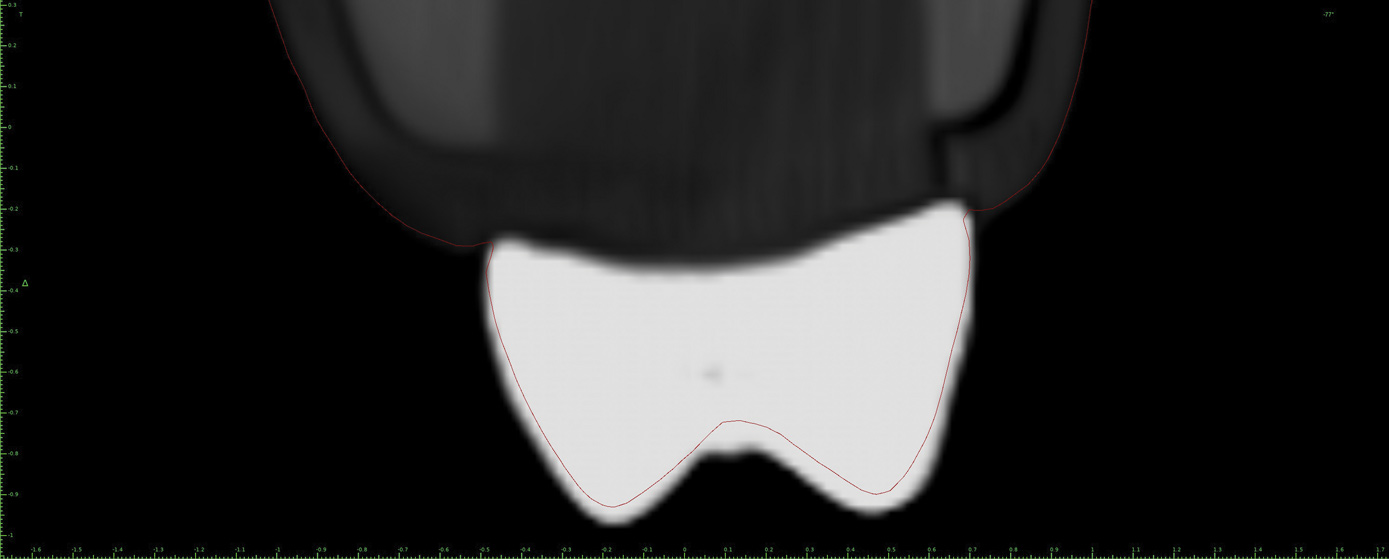

Fig 13. Thin (0.2 mm) slice at the level of the maxillary right first molar shown in Fig 12 with the STL file of the surface model registered. In this case no scanning appliance was used. Note the blooming effect produced by the artifacts at the level of the first molar.

Figure 13